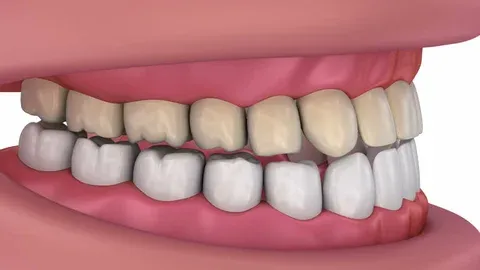

Solution : Whitening, Intracanal Whitening, Home Whitening, Porcelain Veneer